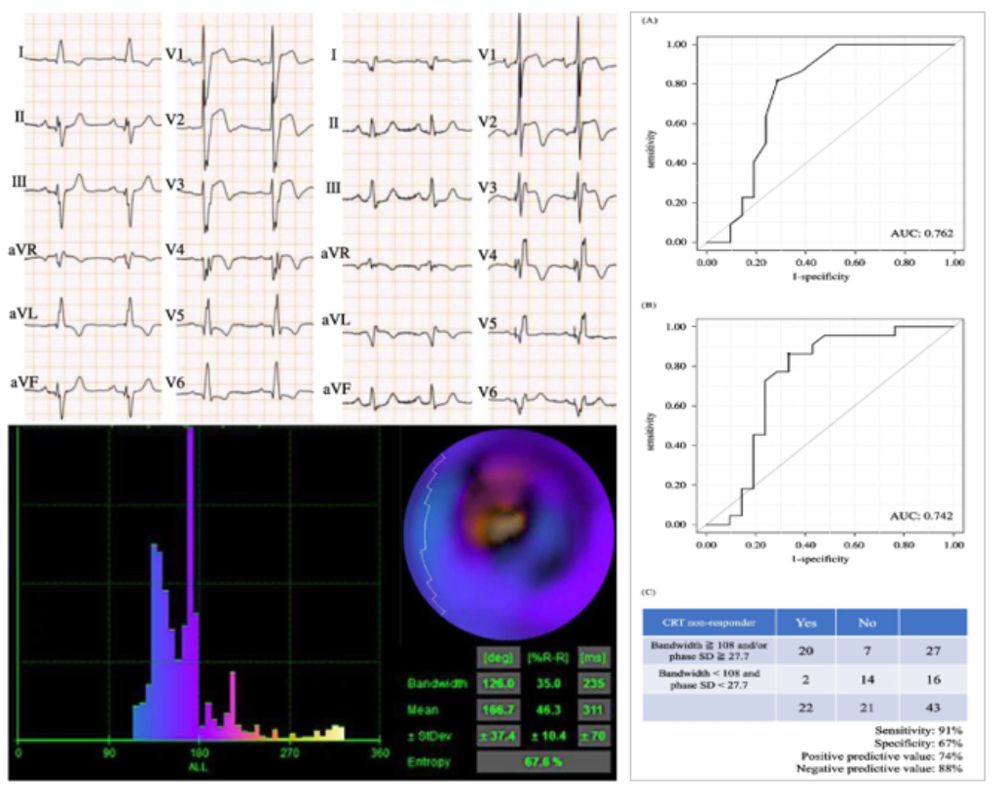

Identifying Non-responders to Cardiac Resynchronization Therapy in the Non-Left Bundle Branch Block

by T Nakamura, S Oka, Y Miyazaki, A Wakamiya, K Nakajima,

K Tsukasa, M Wada, Y Inoue, S Nagase, T Aiba & K Kusano